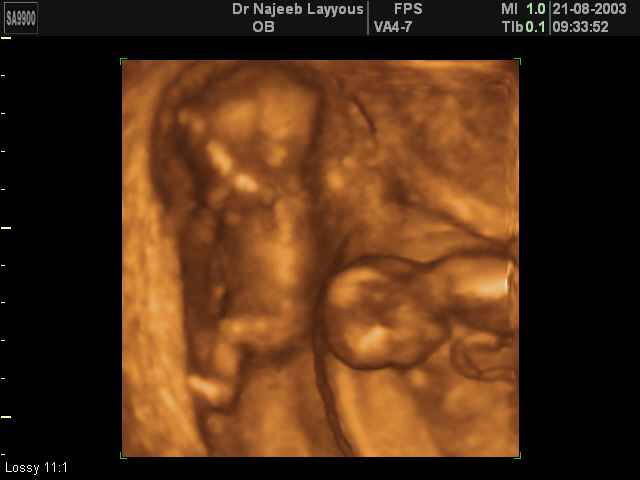

شوفوا صور التراساوند حقت التوينز

هنا حمل توينز عمره 5اسابيع

اجنة توام عمرهم سبع اسابيع

اجنة توام عمرهم 11 اسبوع

شوفوا هذول واحد يدف اخوه يا حلوهم